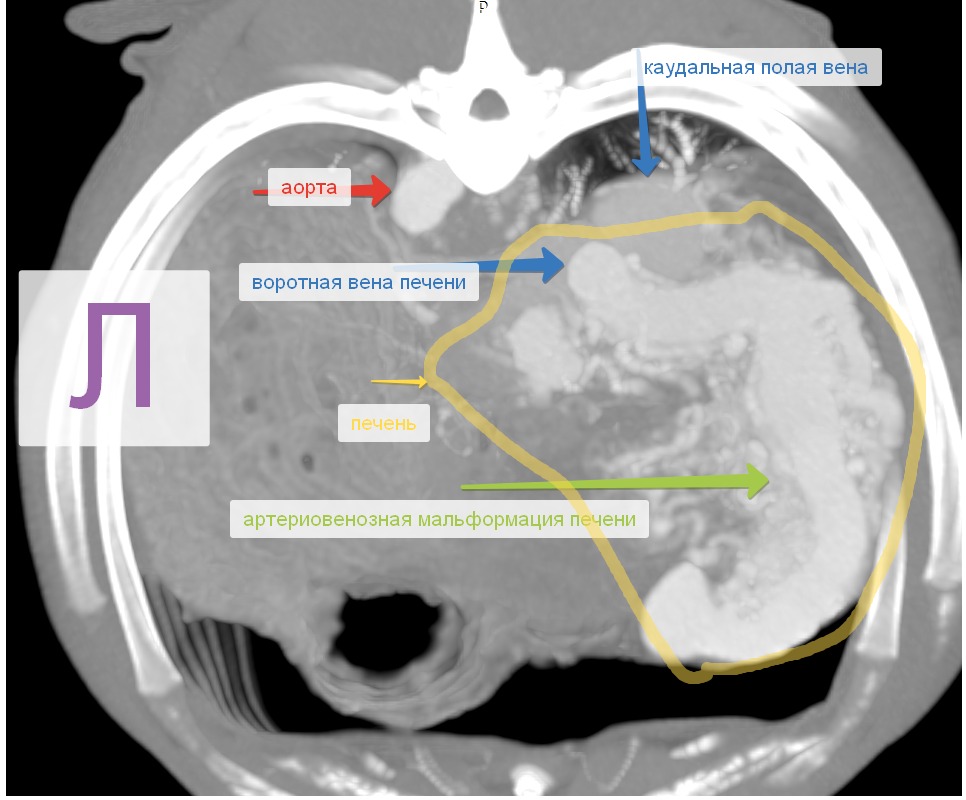

АВМ печени принято делить на правосторонние и левосторонние. Последние подразделяются на левую латеральную и медиальную мальформации в зависимости от положения выносящей вены (рис. 2).

Печеночные АВМ чаще диагностируются у собак, чем у кошек, и представляют собой соединения ветвей печеночной артерии и портальной вены. Артериализация портальной вены приводит к гипертензии, что способствует развитию множественных внепеченочных шунтов. Асцит является частой находкой при печеночных АВМ. Врожденные АВМ в основном сопровождаются симптомами печеночной энцефалопатии, портальной гипертензии и желудочно-кишечных расстройств.

Диагностика печеночных АВМ осуществляется с применением КТ-ангиографии, выявляющей сосудистую сеть (или «гнездо»), образованную ветвями приносящей печеночной, гастродуоденальной, левой желудочной и другими артериями, через которую происходит слияние с воротной веной (рис. 3). Артериальная фаза является самой важной в идентификации приносящих ветвей артериовенозной мальформации. АВМ имеют тенденцию изменяться со временем, в связи с этим КТ-ангиографию рекомендуют проводить как можно ближе к дате планируемого хирургического вмешательства.